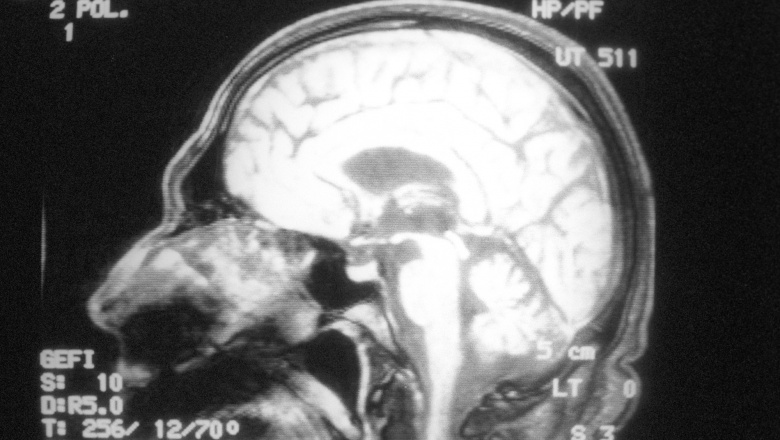

В мозге людей нашли магнитные шарики

Исследователи из Ланкастерского университета в Великобритании обнаружили микроскопические магнитные частицы в мозге людей. Ученые считают, что они попали в нервные ткани из загрязненного воздуха и могут быть возможной причиной болезни Альцгеймера. Результаты исследования опубликованы в журнале Proceedings of the National Academy of Sciences.

Многочисленные наночастицы магнетита были найдены у 37 человек, которые жили в Мехико (Мексика) и Манчестере (Великобритания). Этот широко распространенный минерал является токсичным и приводит к возникновению в клетках активных форм кислорода (свободных радикалов).

Ученые с помощью спектроскопического